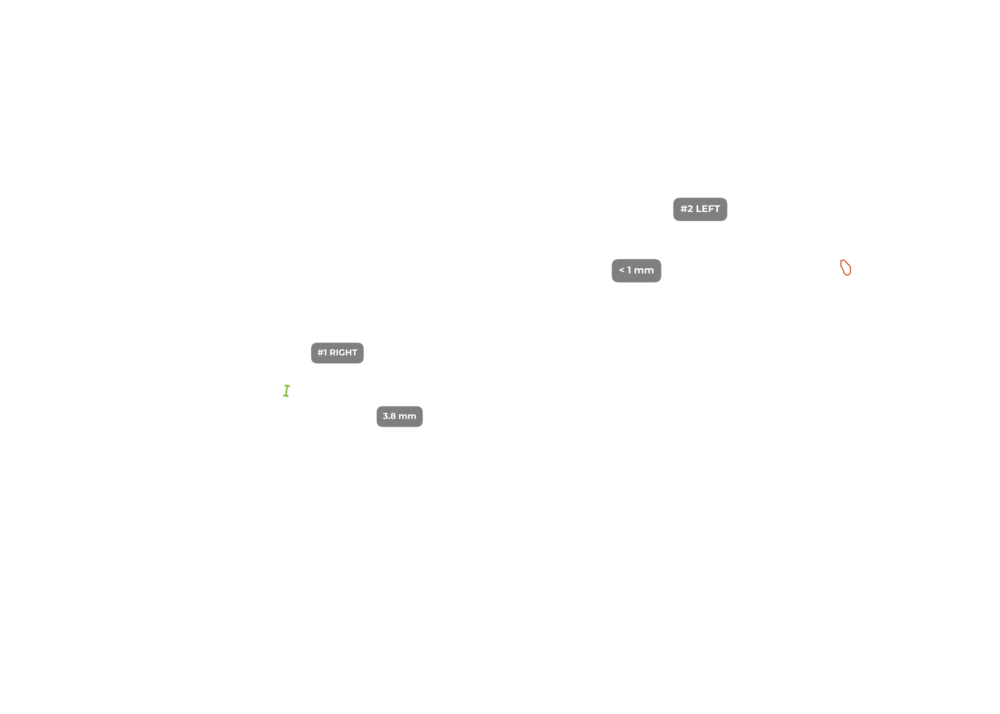

ИИ и алгоритмы интеллектуального анализа рентгеновских снимков позвоночника. Позволяет обнаружить математически обоснованные искривления позвоночника и костные аномалии менее чем за 30 секунд

ИИ и алгоритмы интеллектуального анализа для рентгена коленного сустава. Оцените дегенеративные процессы менее чем за 1 минуту

ИИ и алгоритмы интеллектуального анализа для рентгена тазобедренного сустава. Оценка дегенеративных процессов менее чем за 1 минуту